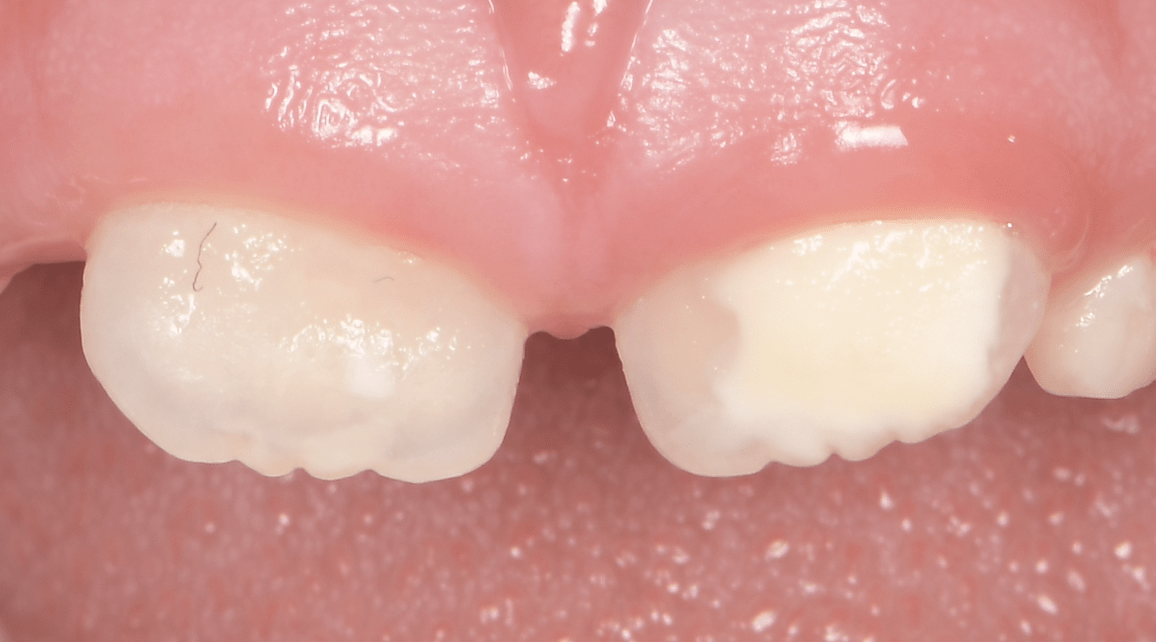

Le congrès de l’EAPD (Académie Européenne d’Odontologie Pédiatrique) a défini des critères de diagnostic en 2003. A savoir des opacités délimités, des fractures post-éruptives, des restaurations atypiques ainsi que que des extractions des molaires. (3) Le diagnostic différentiel doit surtout s’établir entre des amélogénèses imparfaites et des hypominéralisations d’origine traumatique pour les dents antérieures. Cliniquement, les dents vont présenter des colorations blanches ou brunes opaques sur une partie ou sur toute la surface de la dent (Figures 1-2-3-4).

formation dentaire pédodontie Figure 3.

Figures 1-2 : Incisives centrales atteintes de MIH

Figure 3-4 : Molaires atteintes de MIH (HSPM + MIH pour la figure 3)